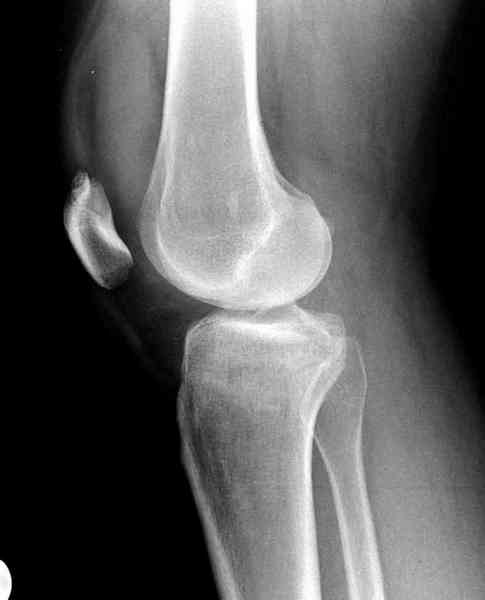

Вложение не в текстовом формате было извлечено…

Имя     : 2 lat tib plateau lat.jpg

Тип     : image/jpeg

Размер  : 16876 байтов

Описание: отсутствует

Url     : http://weborto.net:8080/pipermail/ortho/attachments/20100926/dbcec959/attachment-0013.jpg